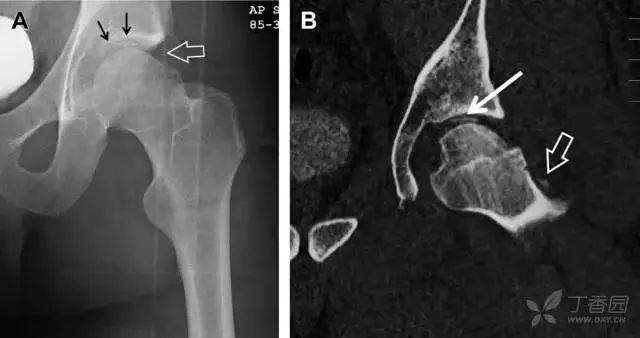

股骨头骨折常与髋关节脱位有关。需要注意的是那些既不是因剪力损伤也不是因直接暴力作用造成的骨折。这些类型的骨折可能十分轻微。提倡应用 CT 检查,不仅可诊断骨折,而且能评估关节内骨折碎片的位置(图 6)。

图 6 股骨颈骨折伴髋关节脱位。A 股骨头上外侧轮廓缺失(空箭头)注意嵌入上方关节间隙的骨折碎片(黑色箭头)B 冠状位 CT 多维重建(MPR)证实骨软骨碎片(白色箭头)和关节上方的另一个碎片(空箭头)